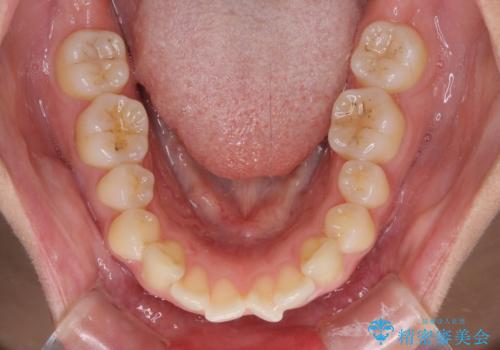

- 前歯の出っ歯と口元の閉じにくさを気にして来院された患者様です。

口元を積極的に引っ込めるために、上下左右の小臼歯4本を抜歯することとしました。

4本の歯を抜歯したことで、飛び出していた口元が引っ込み、横顔が大きく改善されました。

咬み合わせが悪化することのないようにスペースを閉じていくことができ、比較的スムーズに治療を進めることができました。